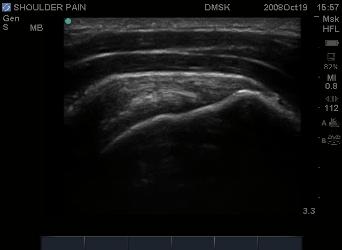

Above: Normal Supraspinatus Tendon insertion.

Image taken with out the Spatial Compounding

Option.  More emphasis is made on probe angle

and beam perpendicularity than if the unit had

the spatial compounding option as seen with the

image on the left.